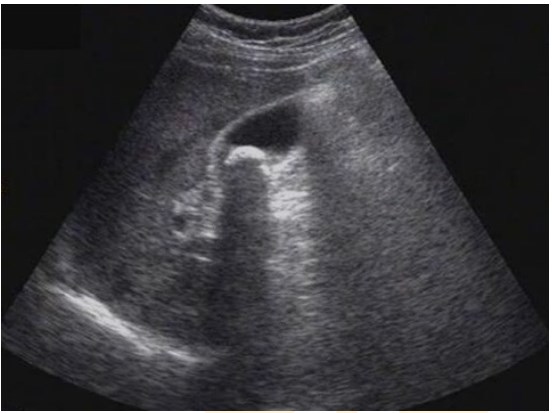

試題:患者女性,50歲,間斷上腹隱痛半年,診斷為(2分)

【答案】C